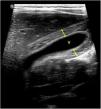

The World Health Organization defines the multisystem inflammatory syndrome in children (MIS-C) as a new syndrome reported in patients aged <19 years old who have a history of exposure to SARS-CoV-2. The onset of this syndrome is characterized by persistent fever that is associated with lethargy, abdominal pain, vomiting and/or diarrhea, and, less frequently, rash and conjunctivitis. The course and severity of the signs and symptoms vary; in some children, MIS-C worsens rapidly and can lead to hypotension, cariogenic shock, or even damage to multiple organs. The characteristic laboratory findings are elevated markers of inflammation and heart dysfunction. The most common radiological findings are cardiomegaly, pleural effusion, signs of heart failure, ascites, and inflammatory changes in the right iliac fossa. In the context of the current COVID-19 pandemic, radiologists need to know the clinical, laboratory, and radiological characteristics of this syndrome to ensure the correct diagnosis.

El síndrome inflamatorio multisistémico pediátrico vinculado a la COVID-19 (SIM-PedS) es, según la Organización Mundial de la Salud, un nuevo síndrome descrito en pacientes menores de 19 años con historia previa de exposición a SARS-CoV-2. La presentación inicial de este síndrome se caracteriza por fiebre persistente que asocia debilidad, dolor abdominal, vómitos y/o diarrea. Menos frecuentemente los pacientes pueden presentar también erupción cutánea y conjuntivitis. El cuadro clínico tiene expresividad y evolución variables, por lo que algunos pacientes pediátricos afectados pueden empeorar rápidamente, desarrollando desde hipotensión y shock cardiogénico a daño multiorgánico. Los hallazgos analíticos característicos del síndrome consisten en elevación de marcadores inflamatorios y disfunción cardíaca. Los hallazgos radiológicos más frecuentes son cardiomegalia, derrame pleural, signos de insuficiencia cardíaca, ascitis y cambios inflamatorios en la fosa ilíaca derecha. En la pandemia actual por COVID-19 es necesario que el radiólogo conozca las características clínico-analíticas y radiológicas de este síndrome para realizar un correcto diagnóstico.